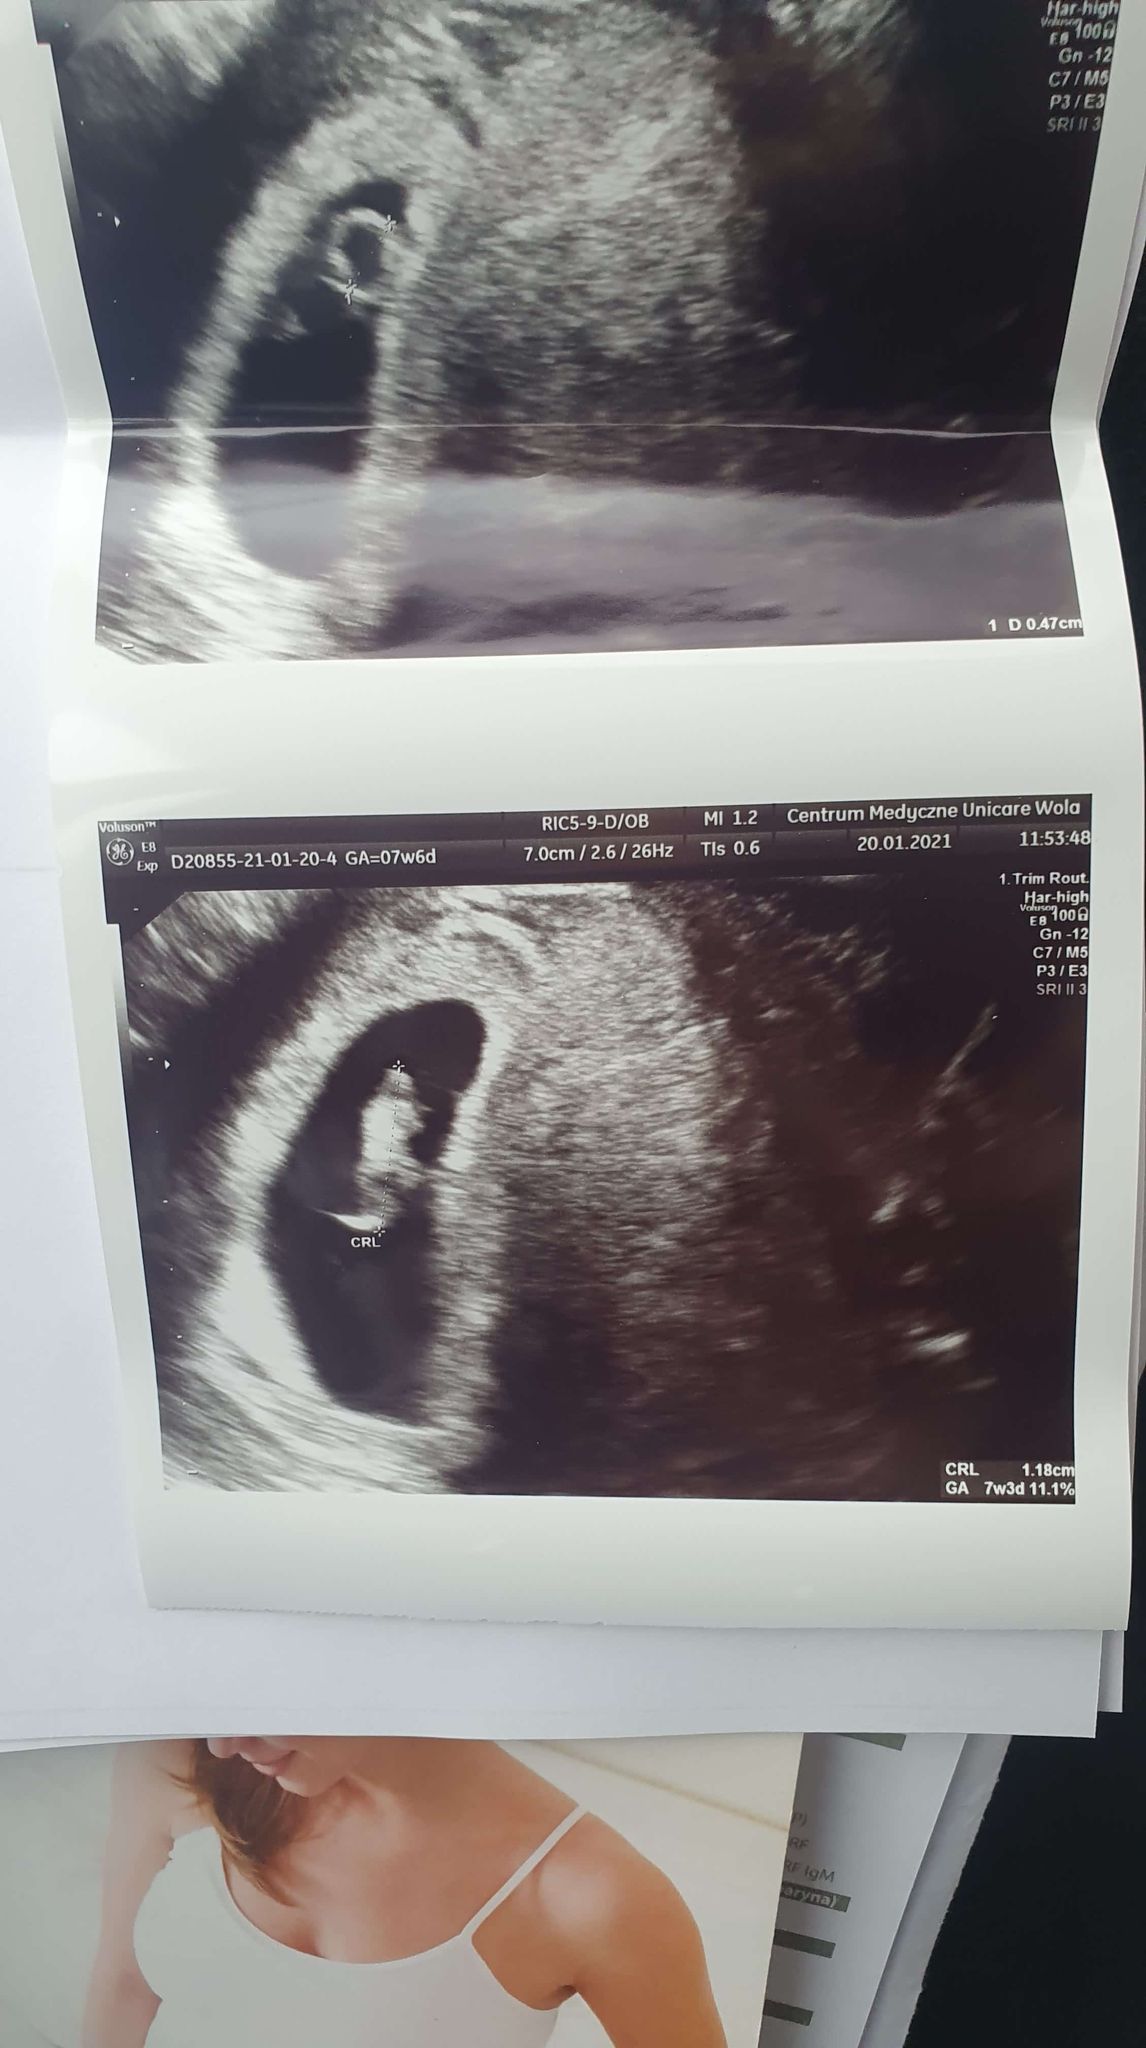

Moja mała fasolka ma 1.2cm

Jestem o wiele spokojniejsza. Pani doktor powiedziała, że wszystko jest w porządku - pęcherzyk żółtkowy 3mm, echo zarodka jest (mężowi nagrałam filmik jak bije maluszkowi serduszko! w końcu uwierzył w tą magię

), trofoblast przylega na całej powierzchni, płyn w prawidłowej ilości. Z jajnika znikła mi torbiel, którą miałam na USG w 6w0d więc się bardzo cieszę - być może ona była powodem plamienia.

Według USG wyszło, że fasolka jest 3 dni młodsza, co jest mega prawdopodobne bo wydaje mi się, że OM w listopadzie była później właśnie o 2-3 dni, więc mamy dzisiaj 7w3d wg USG.